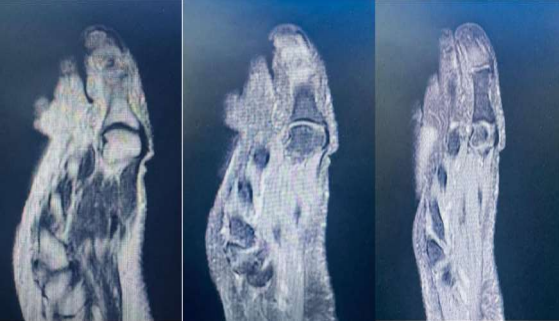

Figure 2: An MRI was requested, showing a hyper-signal at the base of distal phalanx of the big toe.

Figure 2